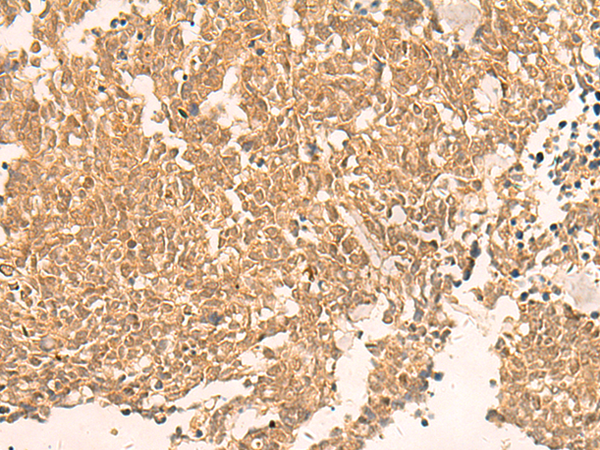

The image is immunohistochemistry of paraffin-embedded Human ovarian cancer tissue using P06719(TRMT112 Antibody) at dilution 1/30. (Original magnification: ×200) |